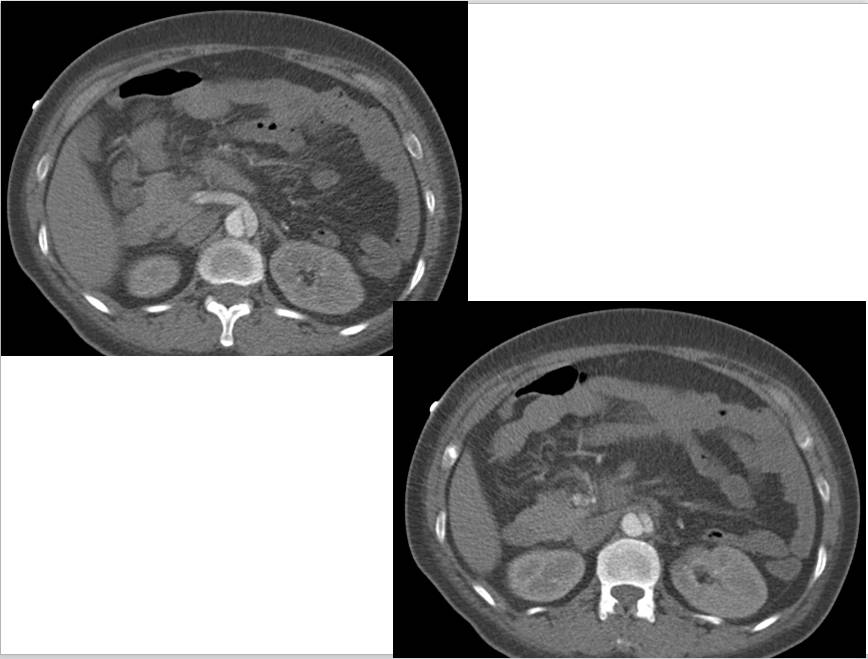

CT表现:自主动脉根部起至腹主动脉肾动脉水平可见撕裂之动脉内膜瓣影,子宫腔内可见胎儿影。

3、真、假腔的显示:真假腔可同时显影,或假腔强化和排空比真腔延迟;假腔内常有血栓形成可呈略高密度影,当多个破口存在时,真假腔较难区分。一般情况下假腔较大,真腔较小。

4、受累分支及范围:确认分支血管供血状况,观察主要器官的供血血管是发自真腔还是假腔。

显示冠状动脉、头臂动脉、腹腔内脏器动脉及髂动脉起源于真或假腔、是否受压推移。如果受夹层累及,可见内膜片线状充盈缺损影自血管开口处伸入分支血管腔内。